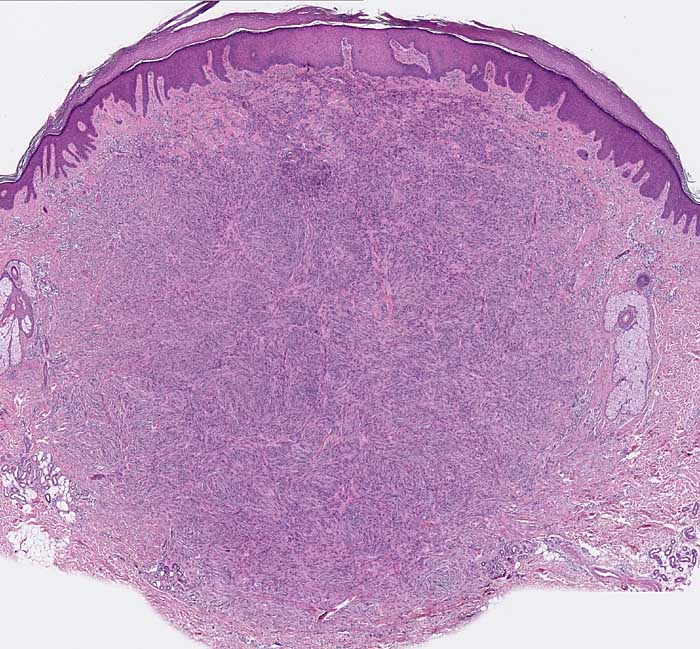

PathoPic ID 7793 - fibröses Histiozytom

fibröses Histiozytom

benigner Tumor

Haut, obere Extremität

Haut

Die Epidermis zeigt eine leichte Hyperkeratose und Akanthose. Von der Epidermis durch eine schmale Kollagenfaserschicht abgegrenzt findet sich in der Dermis ein zellreicher spindelzelliger kugeliger Tumor mit unscharfer Begrenzung.

Derber Knoten am Oberarm

Histologie

25